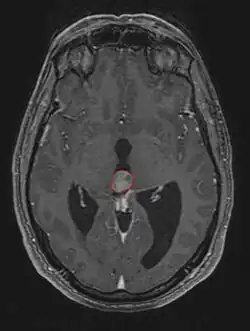

Radiation Oncology/CNS/Pineal

Pineal Gland Tumors

• Work-up includes MRI, CSF, serum markers for bHCG and AFP